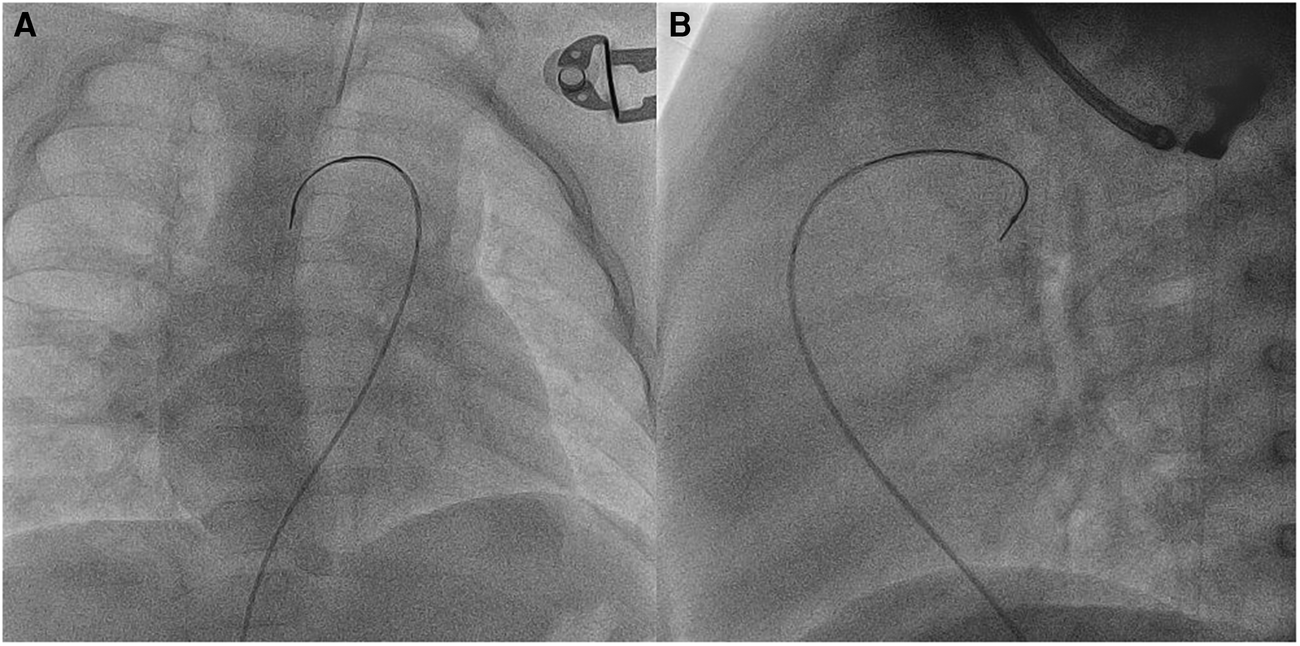

In three patients (no. 2, no. 7, and no. 16) with previously stented arterial ducts, SwiftNINJA was applied to cross the ductal stents transvenously by going across the ventricular septal defect and through the ascending aorta (Figure 5 and Supplementary Video S3). We used the venous approach in these small patients because the French size is more flexible, in case a bigger balloon was needed for the dilation of the stent. In patient no. 11, the ductal stent was oriented upward and protruding in the descending aorta. We used the SwiftNINJA to engage the lumen of the stent without crossing the struts (Supplementary Video S4). In patient no. 14, we accessed transarterially the ductal stent and dilated the narrowed origin of the right pulmonary artery. SwiftNINJA was very helpful in re-accessing the left pulmonary artery, without crossing the stent struts and opening the struts to the left pulmonary artery.

FIGURE 5

www.frontiersin.org

Figure 5. Patient no. 2. Right anterior oblique (A) and lateral (B) views showing SwiftNINJA angulated at a 90-degree angle to cross the ductal stent transvenously after crossing the ventricular septal defect and the ascending aorta.